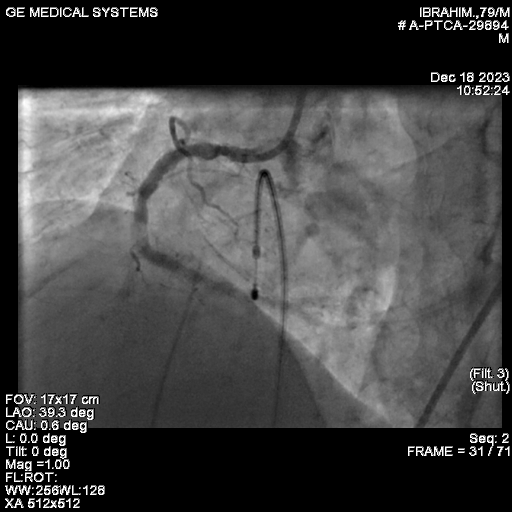

We proceeded with Percutaneous Transluminal Coronary Angioplasty (PTCA) of the Right Coronary Artery (RCA), utilizing ROTAPRO SUPPORT due to the calcified nature of the lesion. The CTO was successfully crossed using a Conquest Pro wire. Intravascular imaging, specifically Optical Coherence Tomography (OCT), confirmed the presence of multiple calcified nodules, highlighting the difficulty of the case.A 1.5 Rotapro was used for preparation.